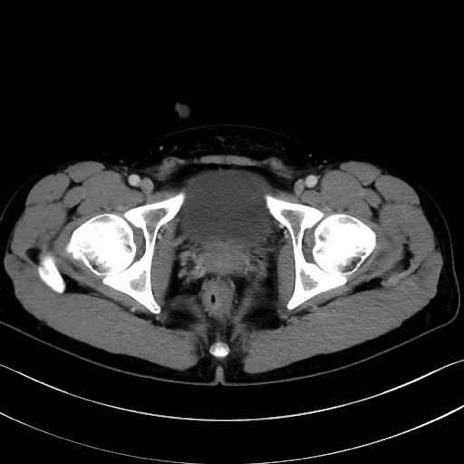

肛門挙筋(levator ani muscle)のCT画像の解剖

肛門挙筋 (Levator ani)